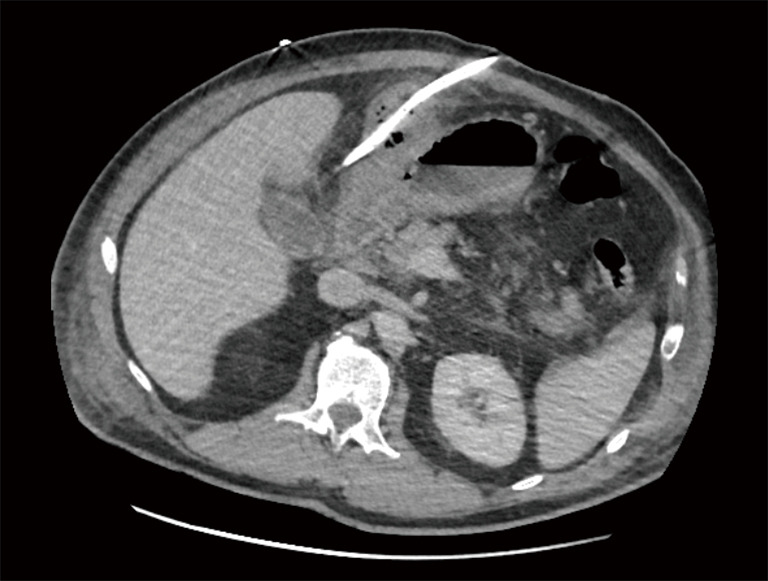

Case description: Here, we present a case of a 61-year-old male, admitted to emergencies with severe abdominal pain and one episode of vomiting. The patient initially diagnosed with mild acute pancreatitis and probable cholecystitis. Because of its severe clinical picture, the patient was admitted to our intensive car unit. Subsequent imaging revealed progression to gangrenous cholecystitis. Decision was taken to drain the gallbladder under computed tomography (CT) scan. Despite antibiotic therapy, the patient developed acute respiratory distress syndrome (ARDS), necessitating intubation. Upon stabilization, an exploratory laparoscopy revealed infected necrosis of the falciform ligament, prompting resection and drainage. Postoperatively, the patient presented a progressive clinical and biological amelioration. The drain was removed and the follow-up was uneventful. A laparoscopic cholecystectomy was scheduled 3 months later.